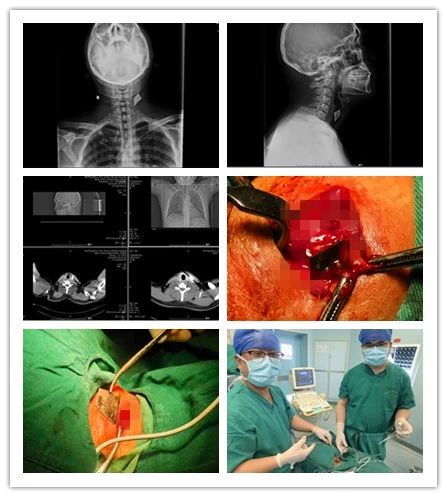

近日,一位“美工刀”刀刺傷的患者來(lái)我院乳腺甲狀腺外科就診,頸部正側(cè)位拍片顯示“美工刀片”深入頸深部,嚴(yán)重危及生命。乳腺甲狀腺外科團(tuán)隊(duì)以十分鐘的“小手術(shù)”成功為患者解除危機(jī),患者現(xiàn)已痊愈出院。

患者,男,35歲,3個(gè)月前頸部被銳器刺傷,傷后出血量約50ml,伴有疼痛,不伴有麻木,呼吸正常,于外院行清創(chuàng)縫合手術(shù),術(shù)后切口反復(fù)感染,并伴有頸部及左側(cè)上肢放射性疼痛,后于我院復(fù)查頸部正側(cè)位片示左側(cè)頸前不規(guī)則致密影,門(mén)診以“左頸部異物”收入院。

乳腺甲狀腺外科王思雷和楊汶士主治醫(yī)師接診后,追問(wèn)患者病史并仔細(xì)檢查,確認(rèn)患者皮膚淺層不存在異物,認(rèn)為異物存在于頸深部,且異物為銳器“美工刀片”,有傷及頸部大血管及氣管、食管可能,隨時(shí)危機(jī)生命,建議手術(shù)取出。但異物位置深,緊鄰頸部大血管、氣管、食管,存在較大手術(shù)難度和風(fēng)險(xiǎn)。科主任李峰和王思雷、楊汶士主治醫(yī)師進(jìn)行充分術(shù)前討論后,制定了周密的手術(shù)方案,在彩超及C臂機(jī)引導(dǎo)下,精確定位,為患者施行頸部異物取出術(shù)+清創(chuàng)縫合術(shù)。術(shù)中發(fā)現(xiàn)異物為銳器“美工刀片”,刀刃鋒利,位置深達(dá)頸椎前側(cè),緊鄰頸部大血管及氣管、食管,差之毫厘便可能造成血管破裂致大出血。兩位醫(yī)師憑借嫻熟的技術(shù),小心翼翼探查,僅用十分鐘便成功取出異物。